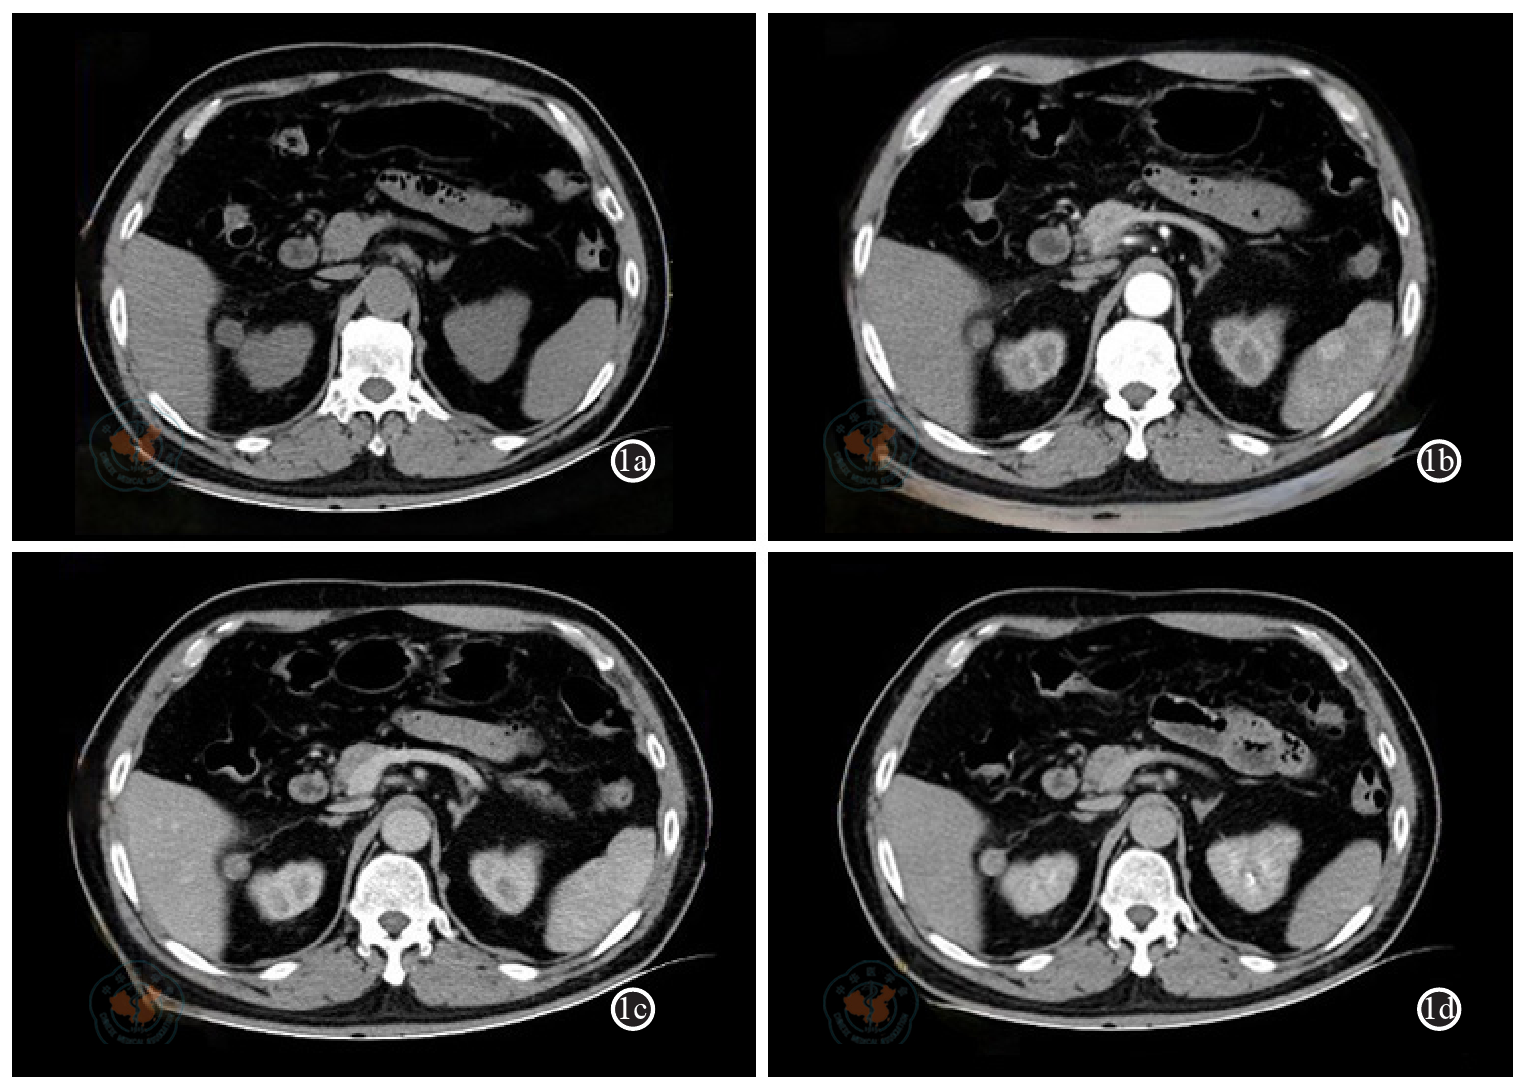

Cheon PM, Rebello R, Naqvi A et al. Anastomosing hemangioma of the kidney: radiologic and pathologic distinctions of a kidney cancer mimic [J].Curr Oncol, 2018, 25(3): e220-e223.